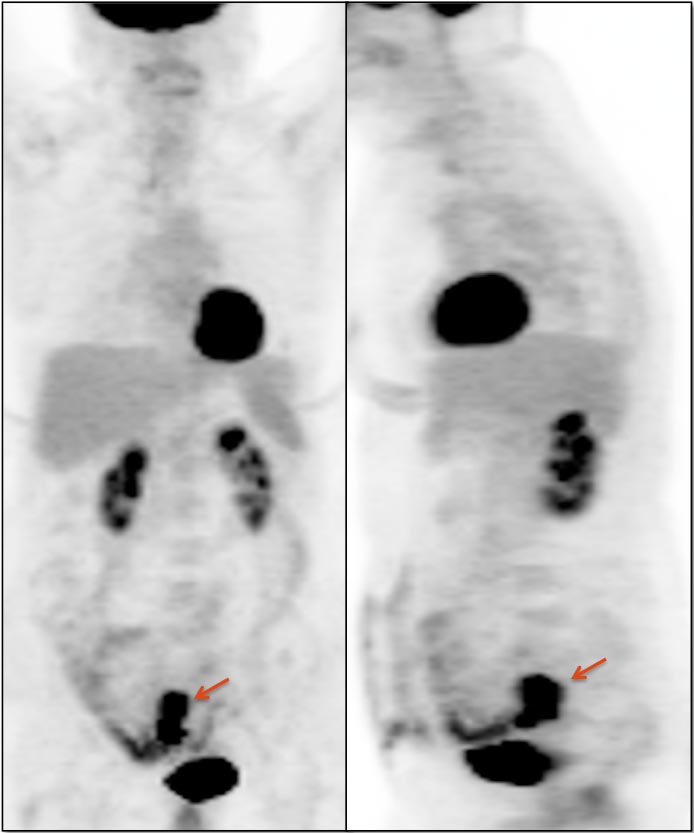

After the stomach, normal intense colon uptake is the most over-called “abnormality” by the inexperienced PET/CT radiologist.

The colon — focally or diffusely — often demonstrates intensely uptake of FDG.

Proposed mechanisms for colonic uptake of FDG include muscle contractions, the presence of lymphoid tissue and intraluminal contents.

The most common sites of normal physiologic intense colon uptake are the cecum and the distal rectum.